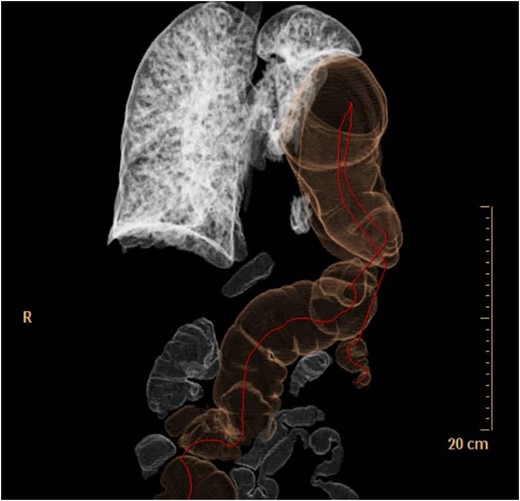

Thoraco-abdominal computed tomography (CT) showed the herniated bowel (transverse colon), translocated through a defect of about 7 cm in the left hemidiaphragm (Figs 2–4), a rightward deviation of the mediastinal structures and an atelectasis of the left lung (Fig. 5). The left colon had the appearance of a volvulus.

CT of chest showing defect on left side of the diaphragm and colon herniation in the thoracic cavity.